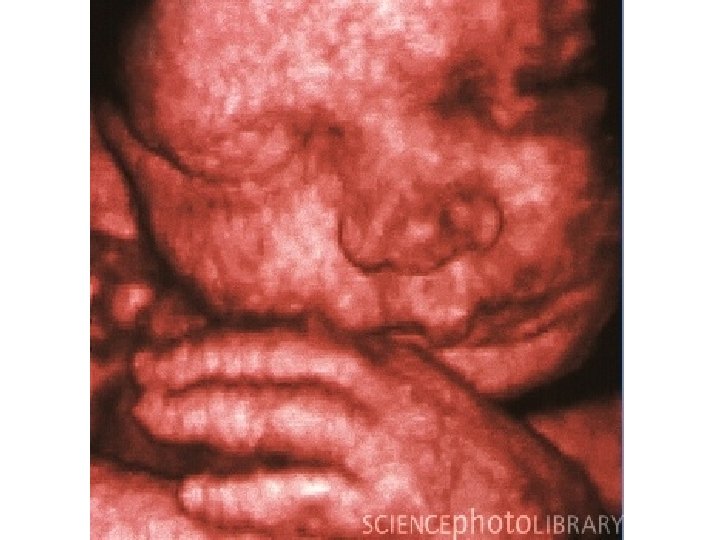

ULTRASOUND uses a technique similar to Navy SONAR to produce diagnostic images. 89

Uses SOUND WAVES (NOT X-RAYS) “real time” images 93

ULTRASOUND uses a technique similar to Navy SONAR to produce diagnostic images. 94

19 Week fetus • http: //images. google. com/imgres? imgurl=http: //e mbryology. med. unsw. edu. au/movies/usound/19 weeklabel 2. jpg&imgrefurl=http: //embryology. med. unsw. edu. au/movies/usound/Hum 19 w 4 D. htm&u sg=__Ef. Di. Z 2 qd. LFEQ_ZGPy 9 YS 628 Qy. PI=&h=3 79&w=358&sz=11&hl=en&start=71&tbnid=Qq. ST byck. VIj. YM: &tbnh=123&tbnw=116&prev=/images%3 Fq %3 Dfetal%2 Bultrasound%26 gbv%3 D 2%26 ndsp %3 D 20%26 hl%3 Den%26 sa%3 DN%26 start%3 D 60 95

2 D vs. 3 D/4 D